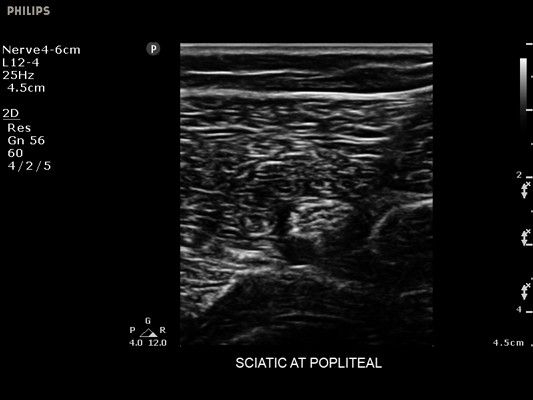

• Диагностика нервов

• Улучшение визуализации иглы для линейных датчиков - Да

• Линейный УЗИ датчик Philips L12-4